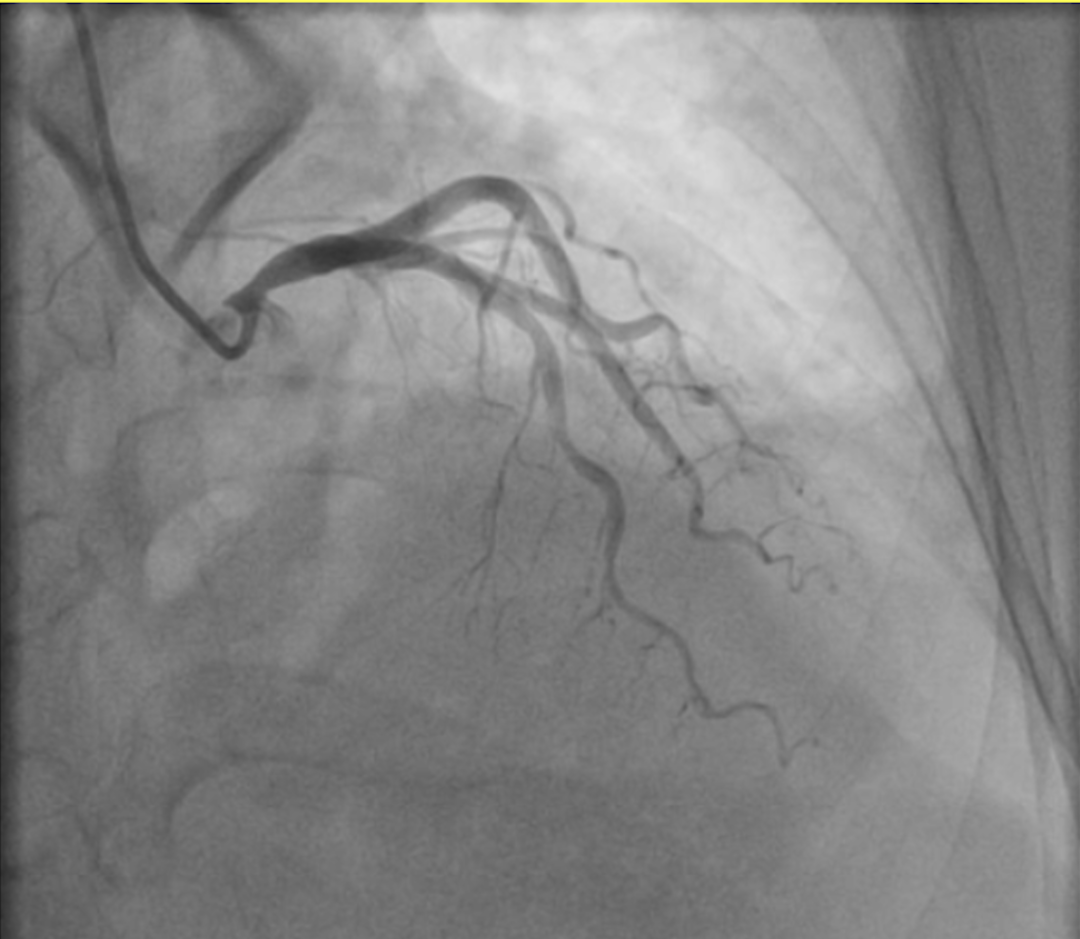

秀洲区人民医院C5病区副主任、心血管内科主任沈奇峰详细询问病史并仔细查体后,安排徐阿姨做了相关检查。冠脉造影显示心脏前降支有约50%狭窄——这个程度通常不会引起持续胸闷症状。这让经验丰富的沈奇峰主任警惕起来:胸闷的元凶,可能不在心脏本身。